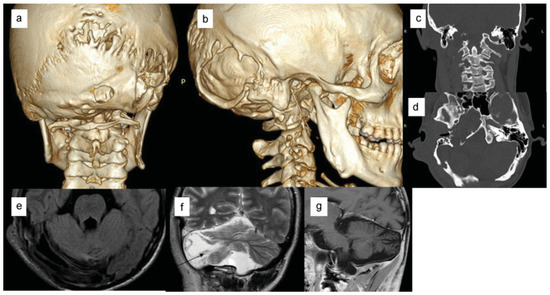

Case Report